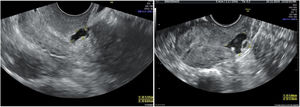

Ante la presencia de un aborto euploide, se decide investigar otras posibles causas de aborto. Se solicita un perfil tiroideo y un estudio de trombofilias, resultando ambos normales. Se estudia también la cavidad uterina con una ecografía transvaginal 3D (las previas fueron siempre, en 2D) y se objetiva en el tercio superior del canal cervical una formación anecogénica de 4,5×3,6×5,9mm compatible con istmocele. Se solicita una histeroscopia, que confirma el diagnóstico, y se plantea la reparación vía histeroscópica. Tras la reparación, la paciente queda gestante de forma espontánea, llegando a tener un recién nacido vivo (fig. 1).